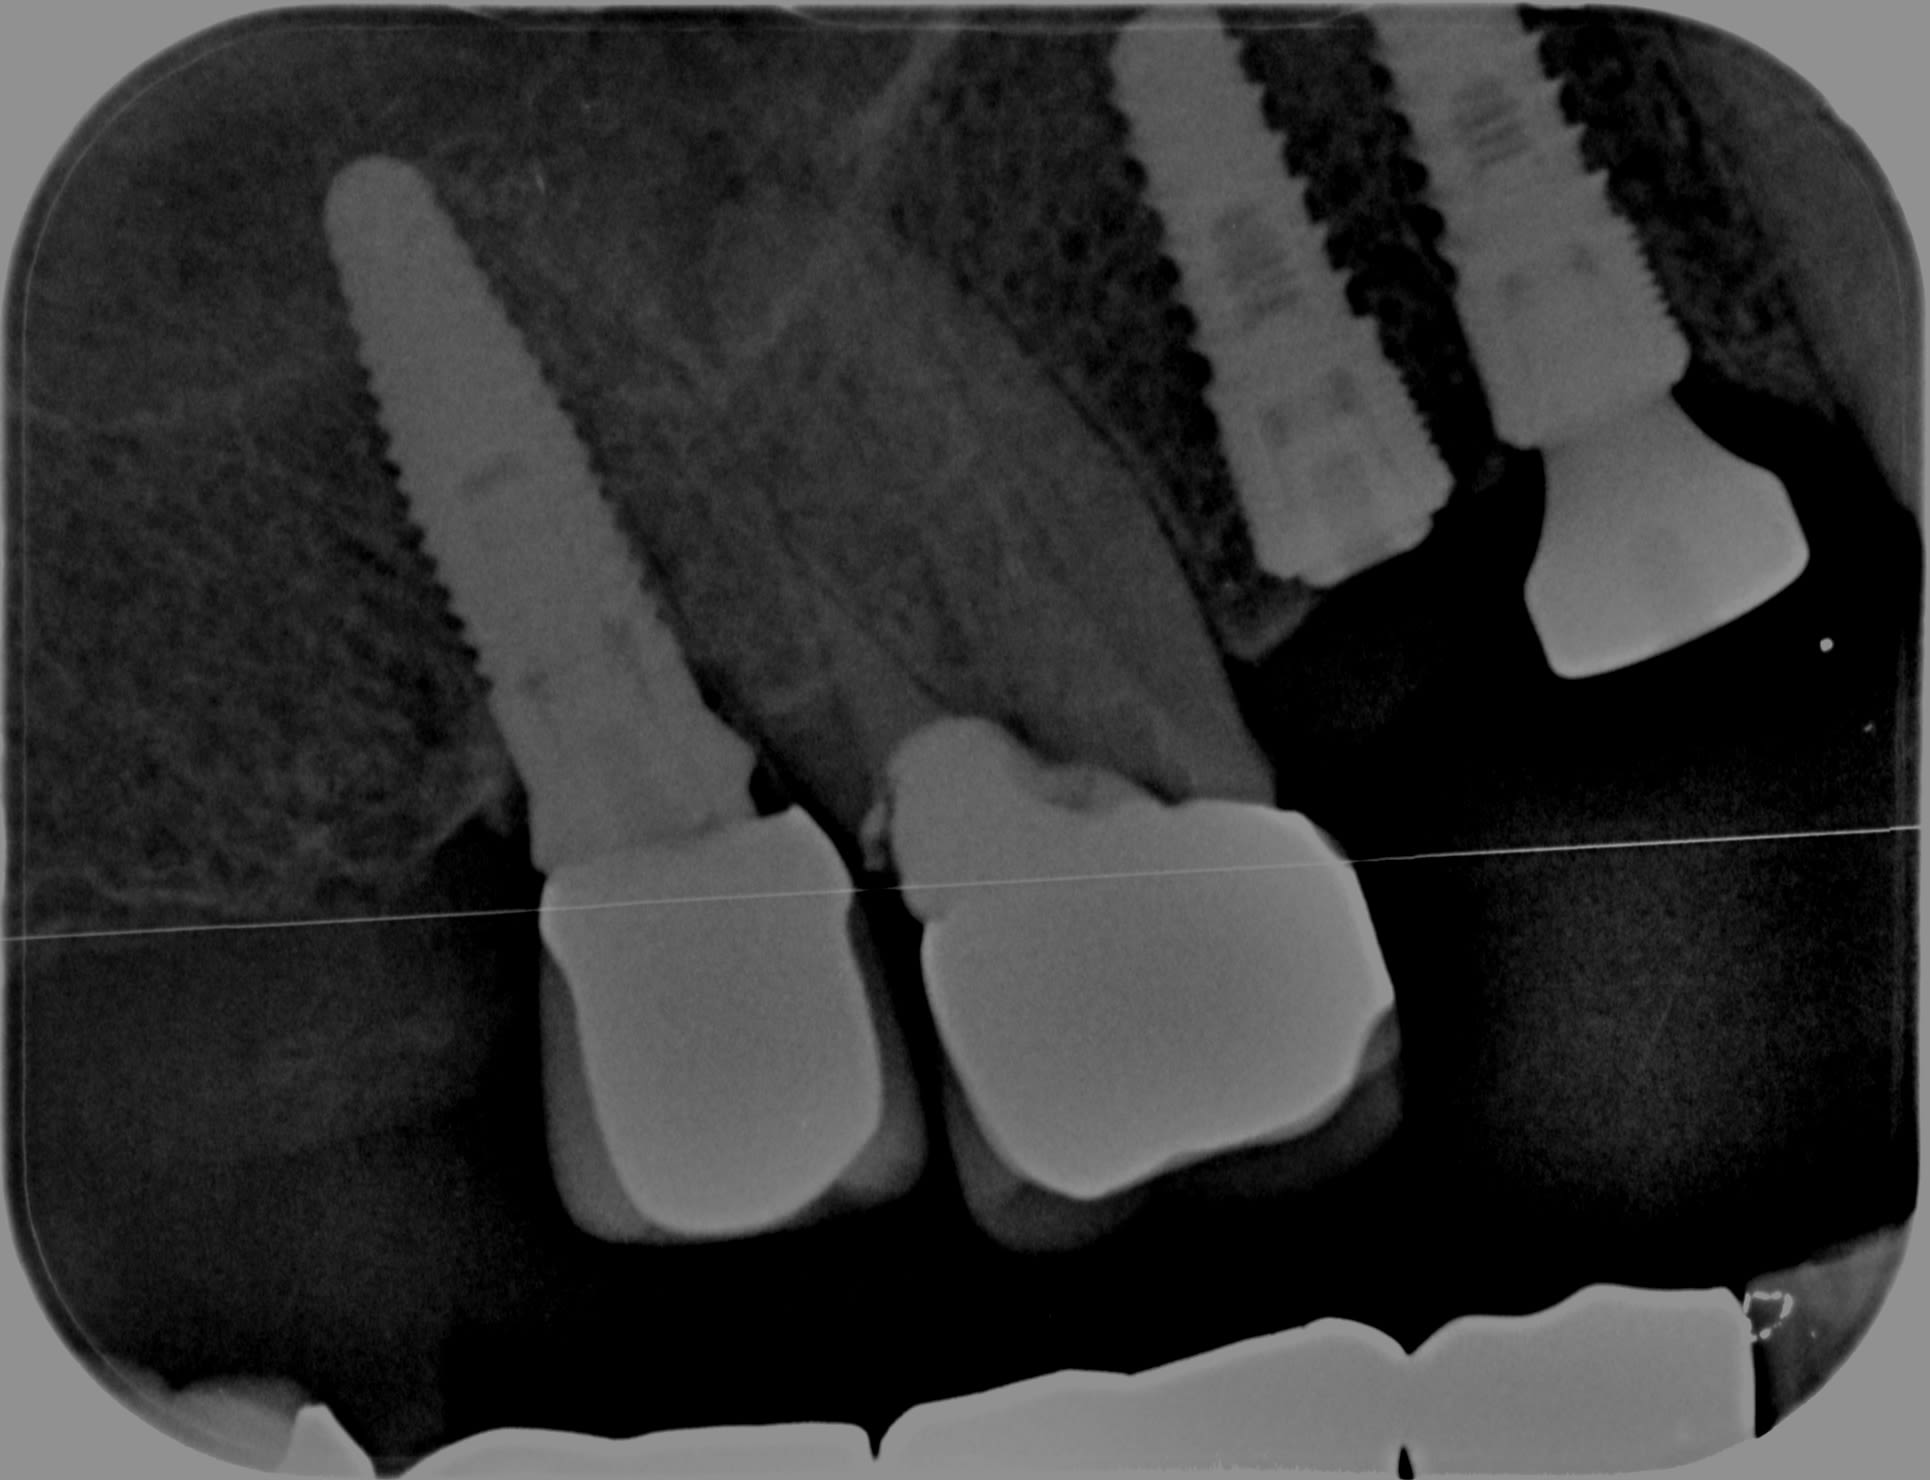

J'ai encore un cas où le poseur est décédé sans successeur... le malheureux ne donnait pas de traçabilité.

J'aimerai bien me servir de l'implant en 17 pour éviter de devoir coller un quatrième implant en 16. (14 et 15 se sont les miens).

Une idée de ce que peut être ce magnifique implant 17?

Un bon petit billet pour un Nobel replace.....;-)

https://whatimplantisthat.com/implants/details/nobelreplace-tapered-groovy-rp